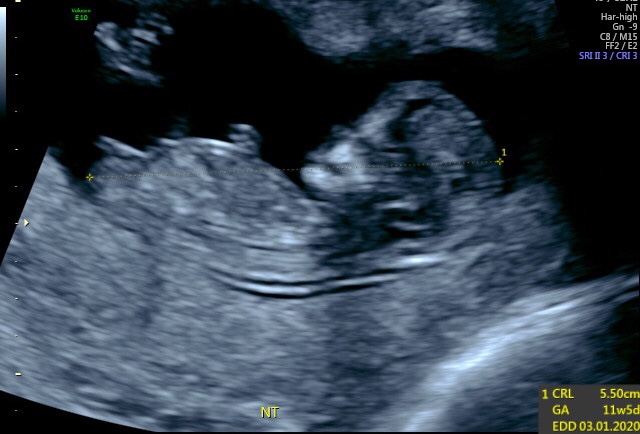

I’m just on 12 weeks and had my ultrasound today. Any guesses? Is it too early to tell?Attachment 41688

I had my 20 week scan and it is definitely a girl [emoji4]